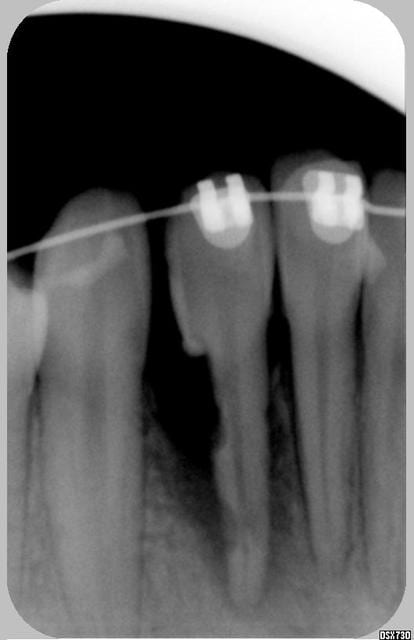

Une jeune patiente(12 ans à l'époque) qui est venue consulter en 06/2003 pour absence de 32 après avulsion spontanée de 72.

J'ai prescris une pano, et au vu de celle ci, la 32 étant enclavée, je l'ai orientée vers un ODF, qui l'a adréssée à un stomato pour dégager la dent.

L'ODF m'adresse la patiente en juin 05 pour que je reconstitue la 32 qui vient d'être repositionnée sur l'arcade.La dent est sensible au toucher avec la sonde,je fais une radio et voilà.

Pour moi la 32 est perdue,et je crains pour la 31....

L'Odf pense que le dent peut"tenir" encore longtemps et qu'elle a été endommagée par le stomato lors du dégagement... et que ce n'est pas la traction .

Déjà préparer psychologiquement le patient et ses parents... Ta radio est un peu sombre, peut-être la résorption est moindre qu'il n'y parait mais bon...

Tu as testé la vitalité, surtout de la 41 qui est peut-être conservable?